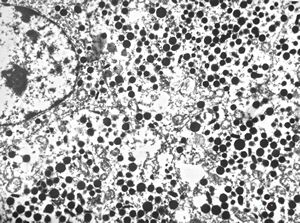

M, 14y. | pheochromocytoma

M, 38y. | pheochromocytoma